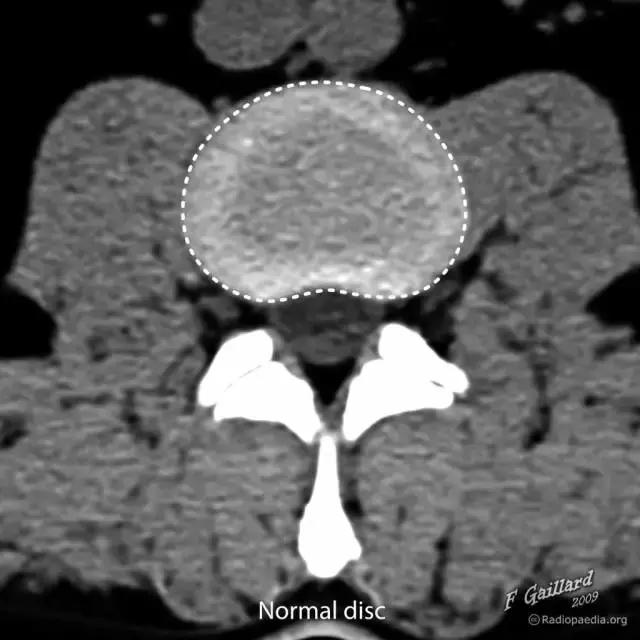

椎间盘是连接相邻两个椎体的纤维软骨盘,由两部分组成,周围部为纤维环(Anulus fibrosis)是由数十层环状及放射状的胶原纤维及弹性纤维交织而成按同心圆排列的致密组织,富于坚韧性,将各椎体紧密牢固的连接成一体,保护髓核并限制髓核向周围突出。

图 1 正常椎间盘示意图,椎间盘由周围的纤维环和中心的髓核组成

图 2 正常椎间盘在相邻两个椎体之间,周围不超出椎体的边缘